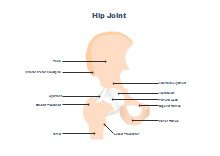

illustrazione scientifica - anatomia umana